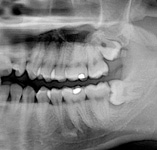

Je speciální zubní digitální tříprostorový tomograf (3D), který umožňuje na základě jediného snímkování vytvořit všechny typy RTG zobrazení, které jsou pro lékaře potřebné. Díky používané technologii tzv. „kuželového paprsku“ a speciálním senzorům je výrazně zmenšená dávka záření - o více jak 80% proti klasickému CT vyšetření. To je významné zejména u dětí. Pomocí tohoto přístroje je možné zjisti skutečnou situaci v čelistních kostech pacienta tedy množství kosti - můžeme změřit skutečnou šířku i výšku kosti, i kvalitu kosti (hustotu) v místě uvažované implantace. 3D (tříprostorové) zobrazení umožňuje zvýšit prostorovou představu operatéra ještě před vlastní operací a zároveň pacientovi lépe objasnit a ukázat oblast plánovaného zavedení implantátu.

Pacient „neumí číst“ RTG snímky, ale díky 3D zobrazení vidí „svoji skutečnou čelist“ - např. jak je nízká či úzká, vidí průběh nervu nebo velikost čelistní dutiny, což mu umožní i pochopení nutnosti v některých případech provést pomocné zákroky ještě před vlastním zavedením implantátu (viz. kostní štěp, sinus lift, kostní granulát...).

Vyšetření pomocí tohoto přístroje používáme i ve stomatochirurgii (zlomeniny čelistí, zuby moudrosti, cysty, onemocnění čelistního kloubu), ortodoncii (retinované zuby, nadpočetné zuby), parodontologii atd.

NewTom Giano

Jedná se o nejnovějším přístroj ze skupiny dentálních hybridních CBCT (3D) + 2D (pan i ceph) systémů. Opět umožňuje na základě jediného snímkování vytvořit všechny typy RTG zobrazení, které jsou pro lékaře potřebné. Používaná technologii tzv. „kuželového paprsku“ a speciální senzory pro minimální zátěž při snímkování pacienta.

Vyšetření pomocí tohoto přístroje (nebo 3D DVT - NewTom) a získaná data používáme pro každou implantaci, dále ve stomatochirurgii (zlomeniny čelistí, zuby moudrosti, cysty, onemocnění čelistního kloubu), ortodoncii (retinované zuby, nadpočetné zuby), parodontologii atd.